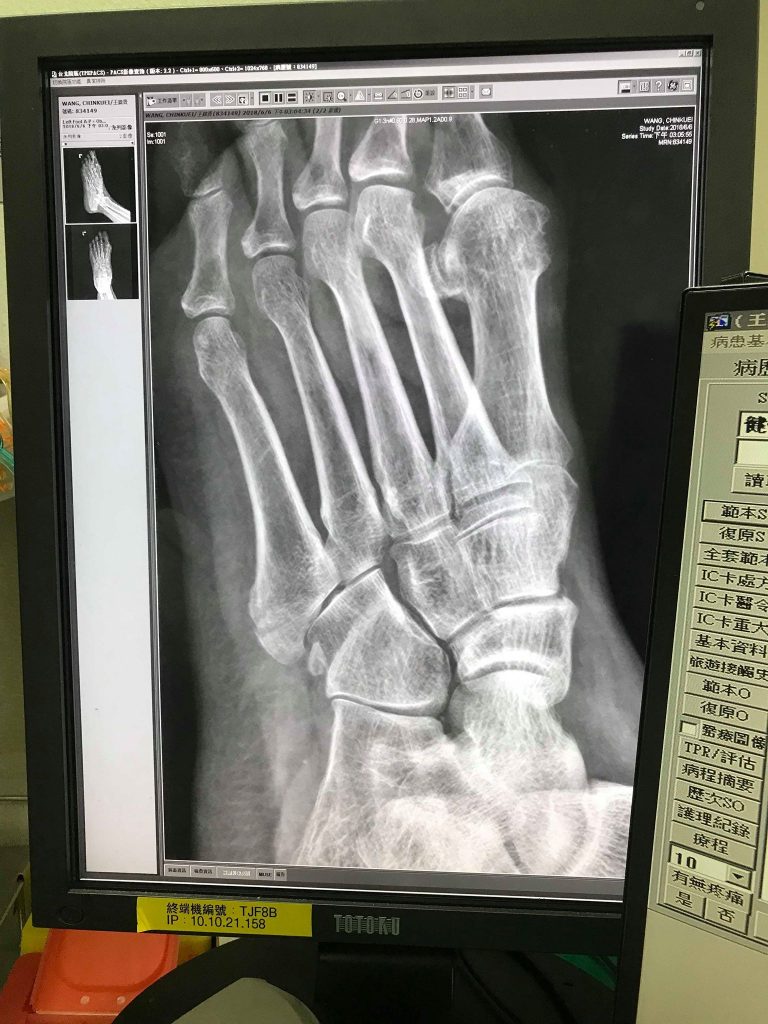

院長大人一照超音波表示有點骨折,

還是要到骨科看一下,

劉醫師看完X光確認骨折,

但不是很嚴重可以先打石膏讓她慢慢長回來,

還好沒去鐵打損傷喬不然很可能要開刀釘釘子了。